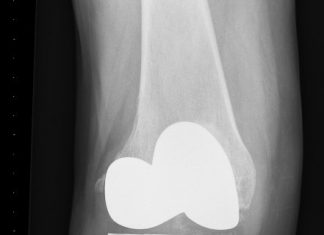

Na drie dagen met een nieuwe knie naar huis

De Sint Maartenskliniek in Woerden is afgelopen week gestart met de invoering van een nieuw hersteltraject voor patiënten die een knieprothese krijgen. Dankzij deze...